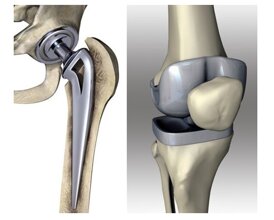

- Protesi articolare: parziale o totale, permette di sostituire le superfici danneggiate restituendo una funzione ottimale e riducendo drasticamente il dolore.

Nelle fasi iniziali, la fisioterapia e le infiltrazioni possono migliorare notevolmente i sintomi; nei casi avanzati, si valuta l’intervento di protesi totale d’anca, oggi eseguito con tecniche mini-invasive e tempi di recupero rapidi.

Il trattamento dipende dallo stadio della malattia: esercizi mirati, fisioterapia, infiltrazioni ecoguidate con acido ialuronico o PRP, fino alla sostituzione protesica nei casi più gravi.

Il trattamento varia dalle infiltrazioni e fisioterapia fino all’impianto di protesi di spalla anatomica o inversa, a seconda della condizione dei tessuti.